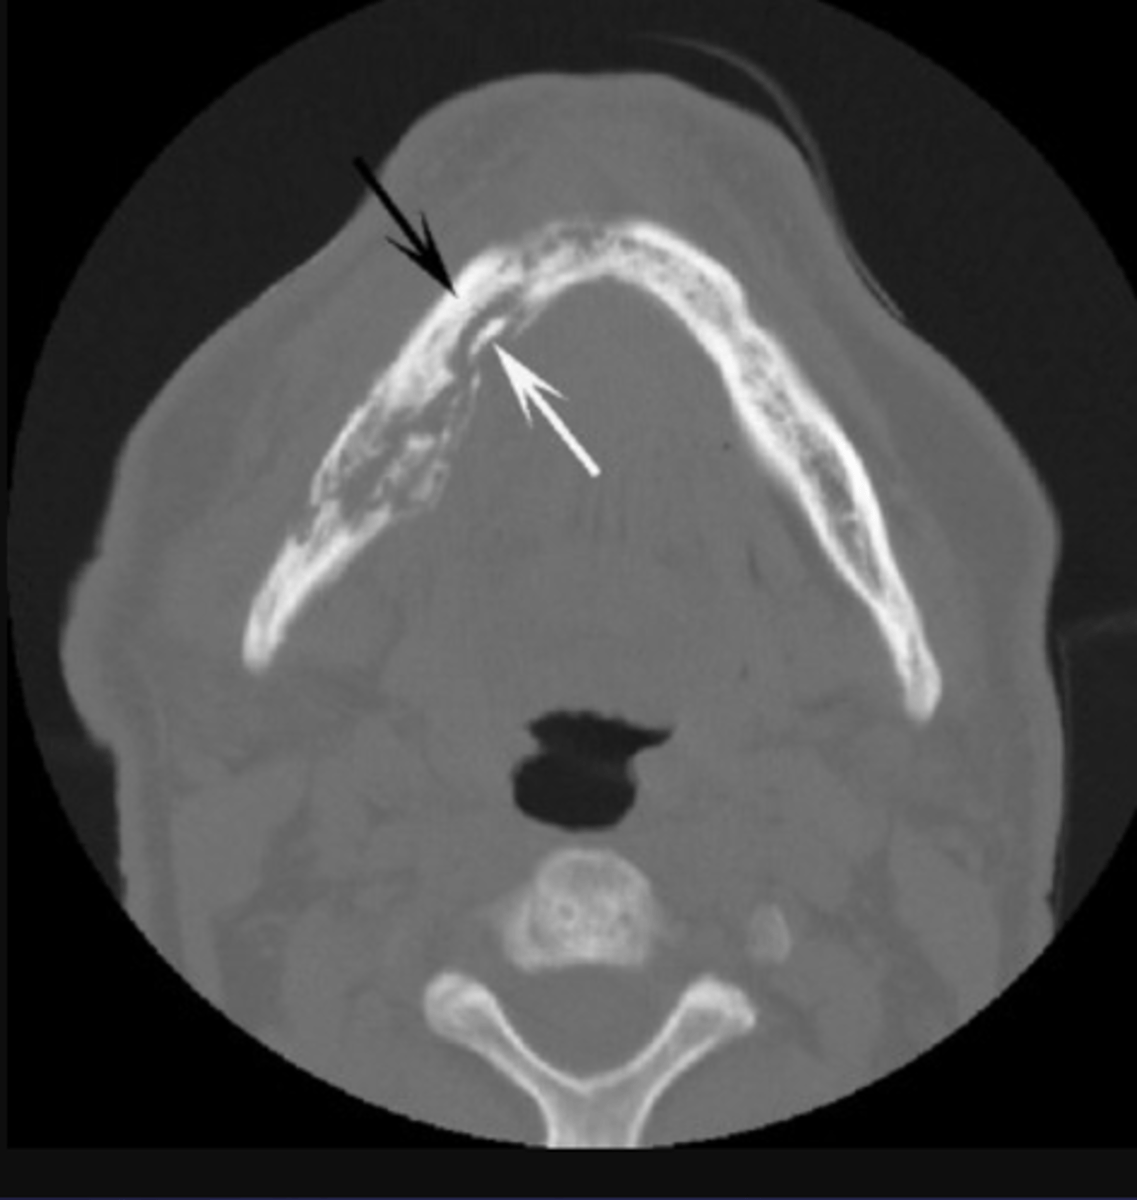

These arrows are pointing at what?

moth-eaten appearance of acute osteomyelitis

The moth eaten appearance is associated with what?

acute osteomyelitis, mixed radiolucent/radiopaque areas